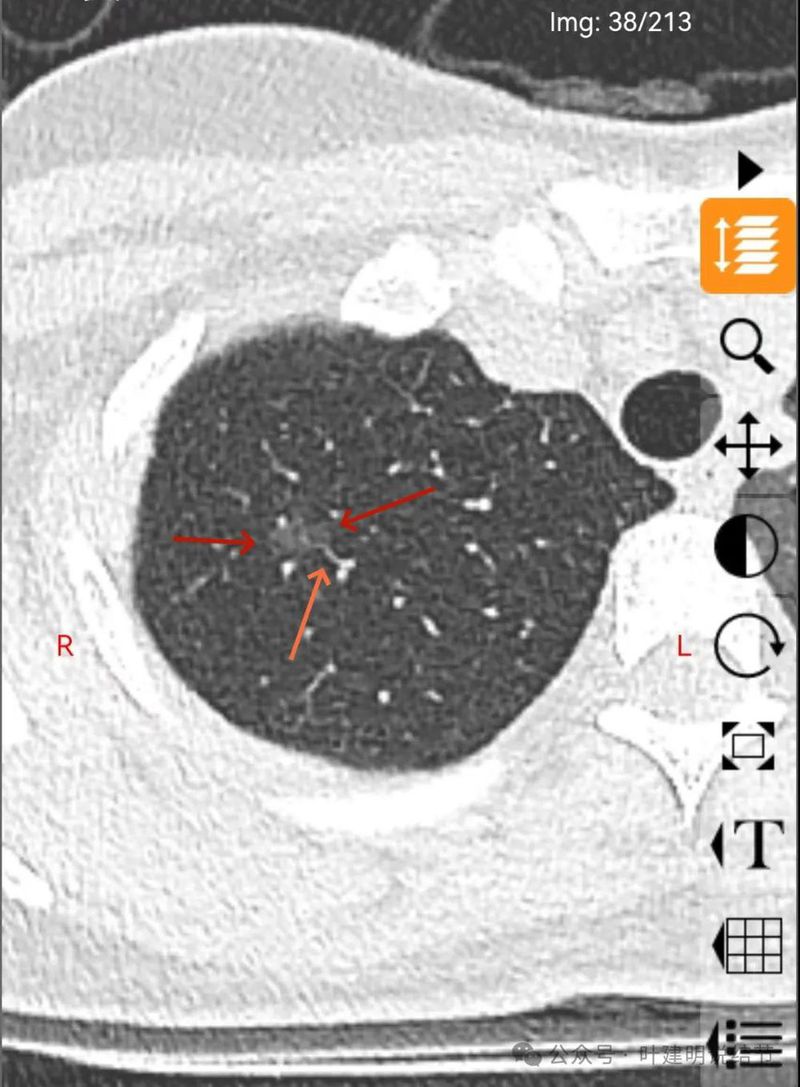

右上叶磨玻璃结节,轮廓较清,密度较淡,有小血管进入。

表面不平,分叶明显,灶边有小空泡征,灶边另有多处血管贴边,也见血管分支进入。